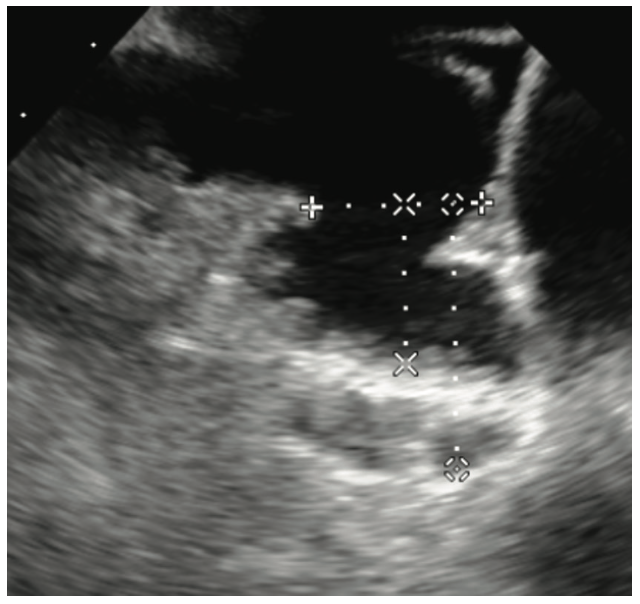

Aside from routine TEE imaging, the preimplantation examination focuses on the LAA dimensions using standardized views derived from the CHAMPION-AF trial.8 In addition to standard views at 0, 45, 90, and 135, each of these views is bisected with a cutting plane. It is also important to document the working depth of the LAA rather than the absolute depth (Figure 1). Measuring both the os and depth of the LAA helps to determine which devices can be offered to the patient. Our institution offers the Amulet, CLAAS System (Conformal Medical), and Watchman FLX device (Table 1). The implanting physician then reviews the images and determines the most appropriate device option.

Using TEE 45 days after implantation, we use the same practices, specific angles for evaluation, and x-plane as in the preimplantation TEE (Figures 2 and 3). We also use a reduced viewing angle to only look at one-half of the device at a time, thus increasing the frame rate. Nyquist limits are reduced to be more sensitive to the lower pressures generated in the LA. The study is read immediately and relayed to the implanting physician. Patients are usually seen in the clinic that afternoon and their anticoagulation regimen is adjusted as needed. Video 1 demonstrates a well-seated Watchman FLX device, and Video 2 shows a well-seated Amulet device.